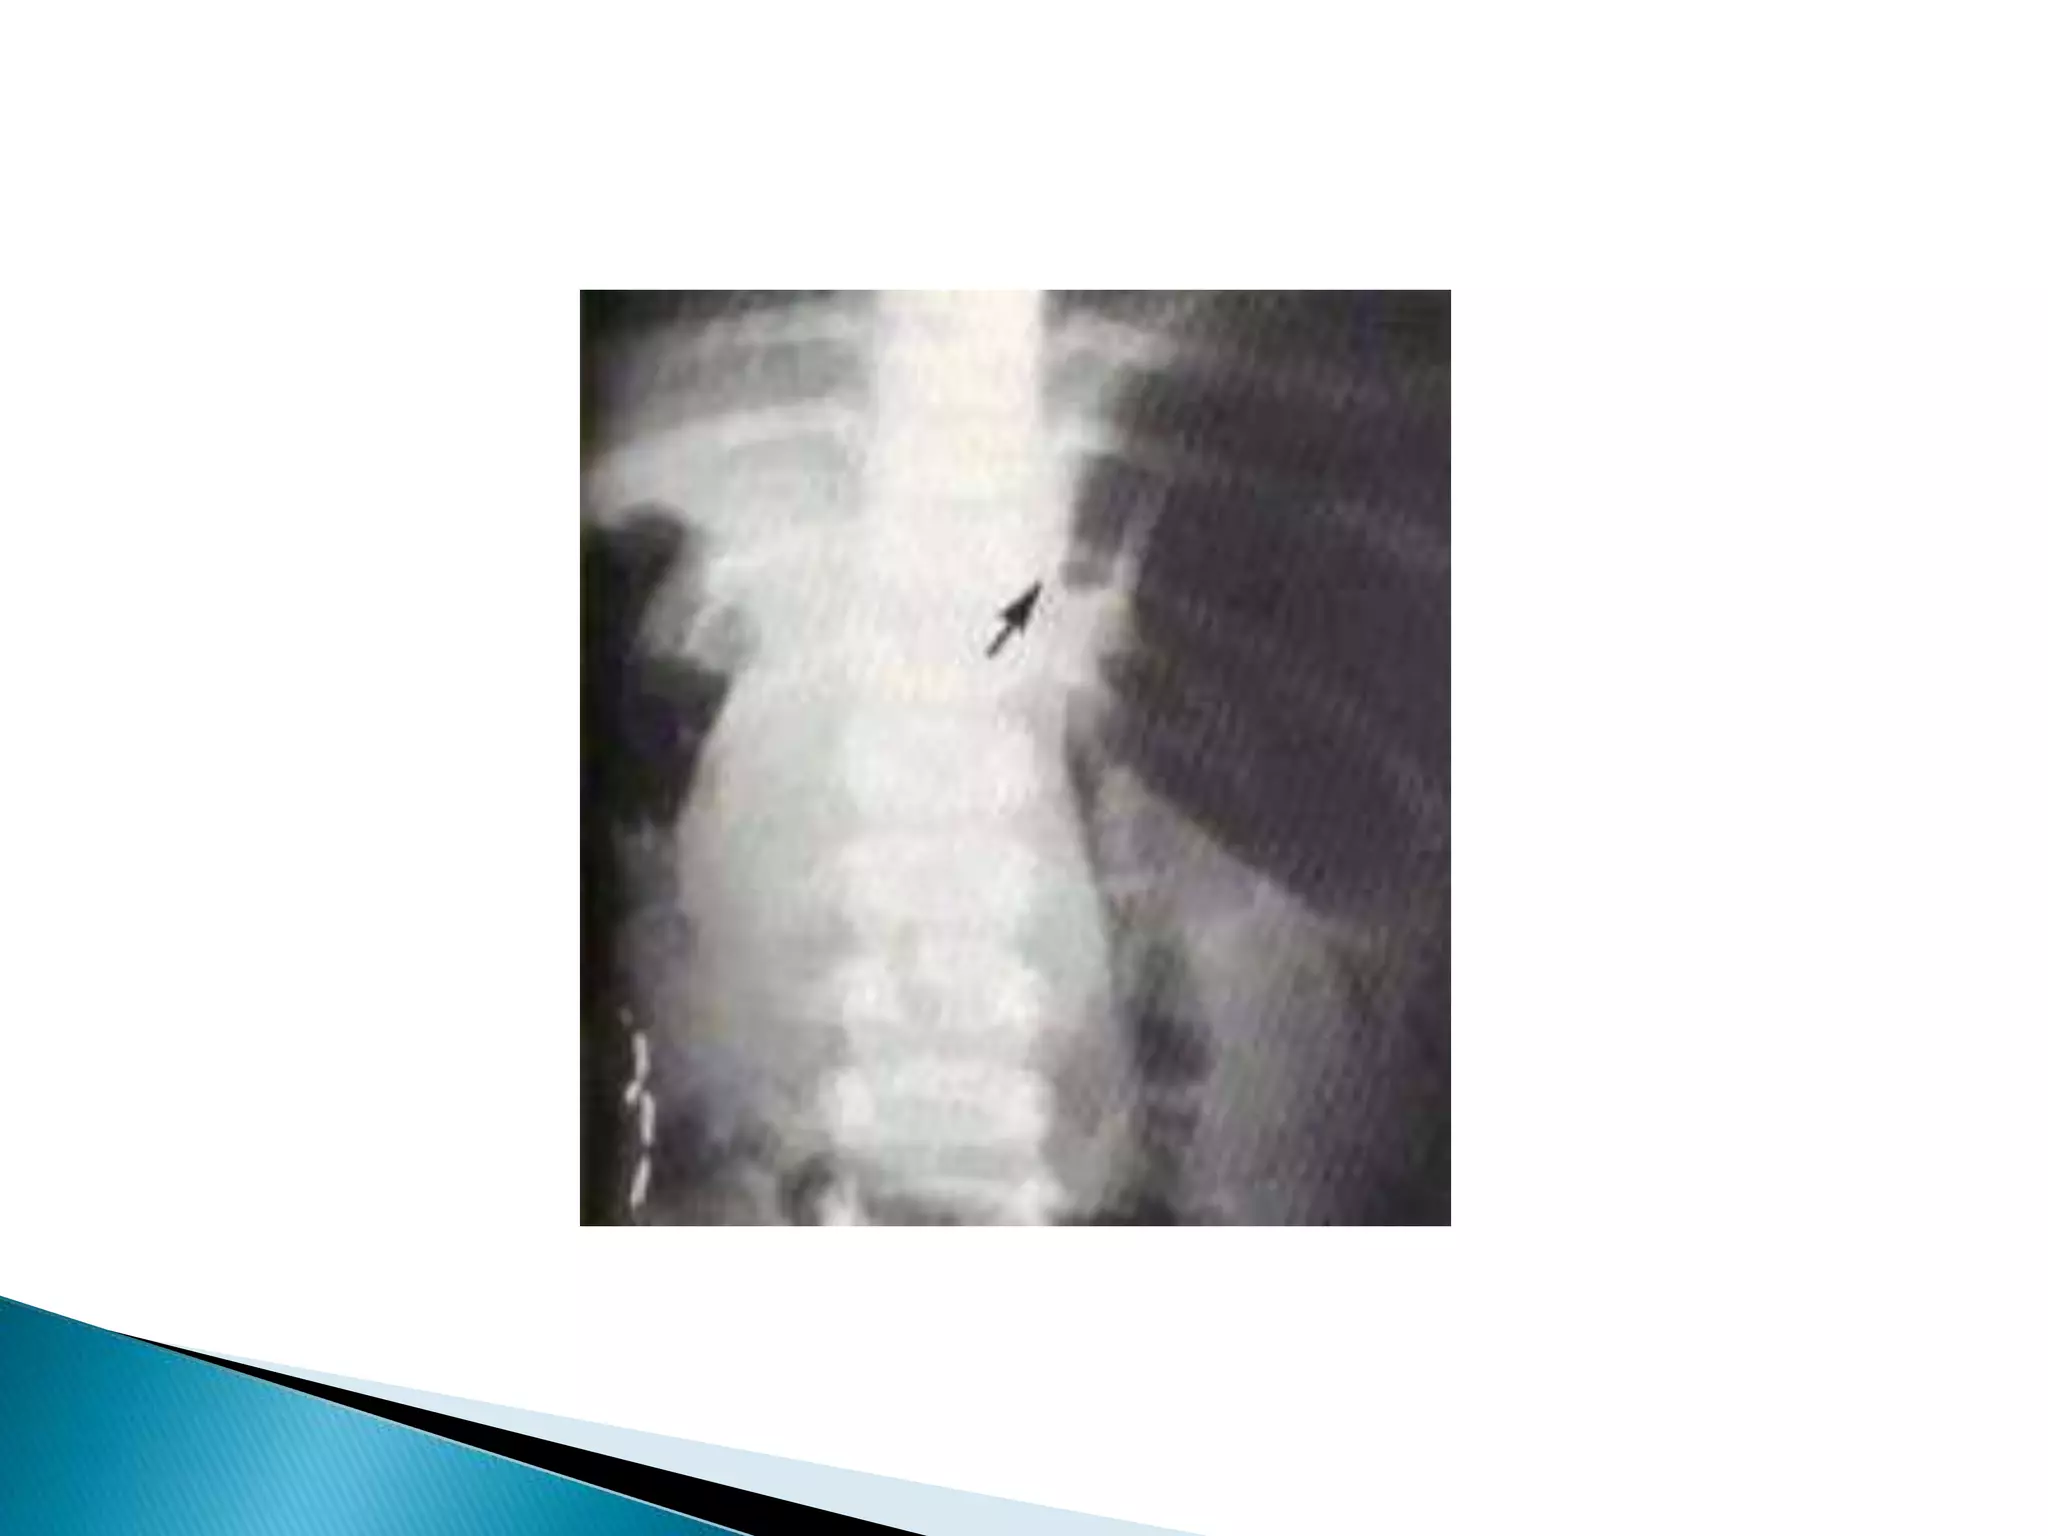

Ba contrast enema

contrast-filled rectum

illustrates the "bird's beak"

sign (white arrow),

corresponding to the

luminal narrowing at the

site of sigmoid obstruction.

This is the characteristic

presentation of a sigmoid

volvulus